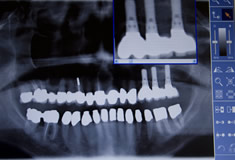

Implantatversorgung

Implantate sind künstliche Zahnwurzeln aus Titan oder Keramik, die mit dem Knochen verwachsen.

In enger Zusammenarbeit mit qualifizierten Implantologen/ Kieferchirurgen fertigen wir in unserer Praxis hochwertigen implantatgetragenen Zahnersatz, d. h. Kronen, Brücken und Prothesen abgestützt auf Implantaten. Das bedeutet für unsere Patienten höchsten Kaukomfort, Sicherheit und Ästhetik.